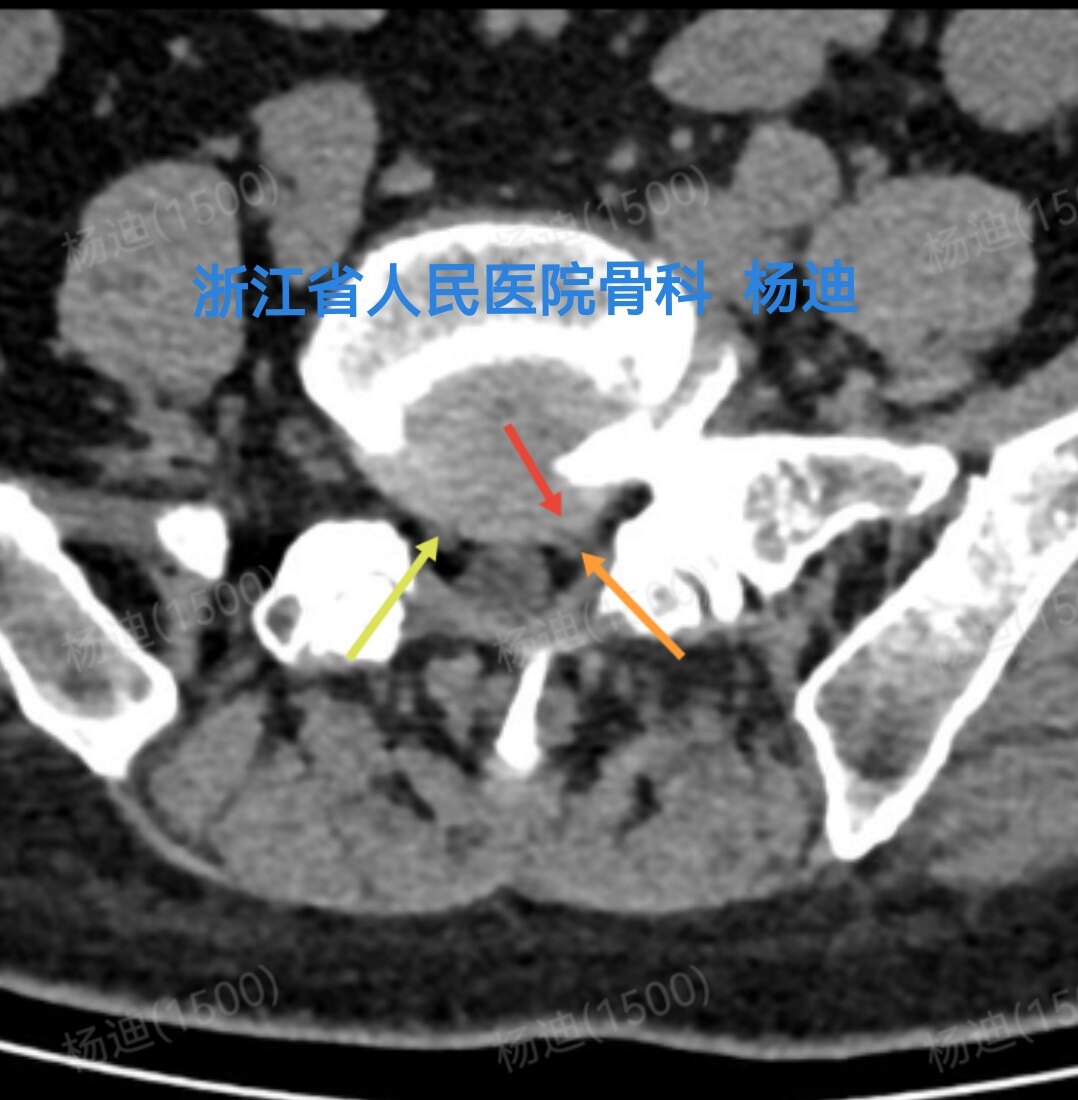

图为磁共振横断面检查:腰5/骶1椎间盘突出(红箭头),左神经根受压(橙箭头),右神经根松弛(黄箭头)

图为CT检查:腰5/骶1椎间盘突出(红色箭头),左神经根受压(橙色箭头),右神经根松弛(黄色箭头)。